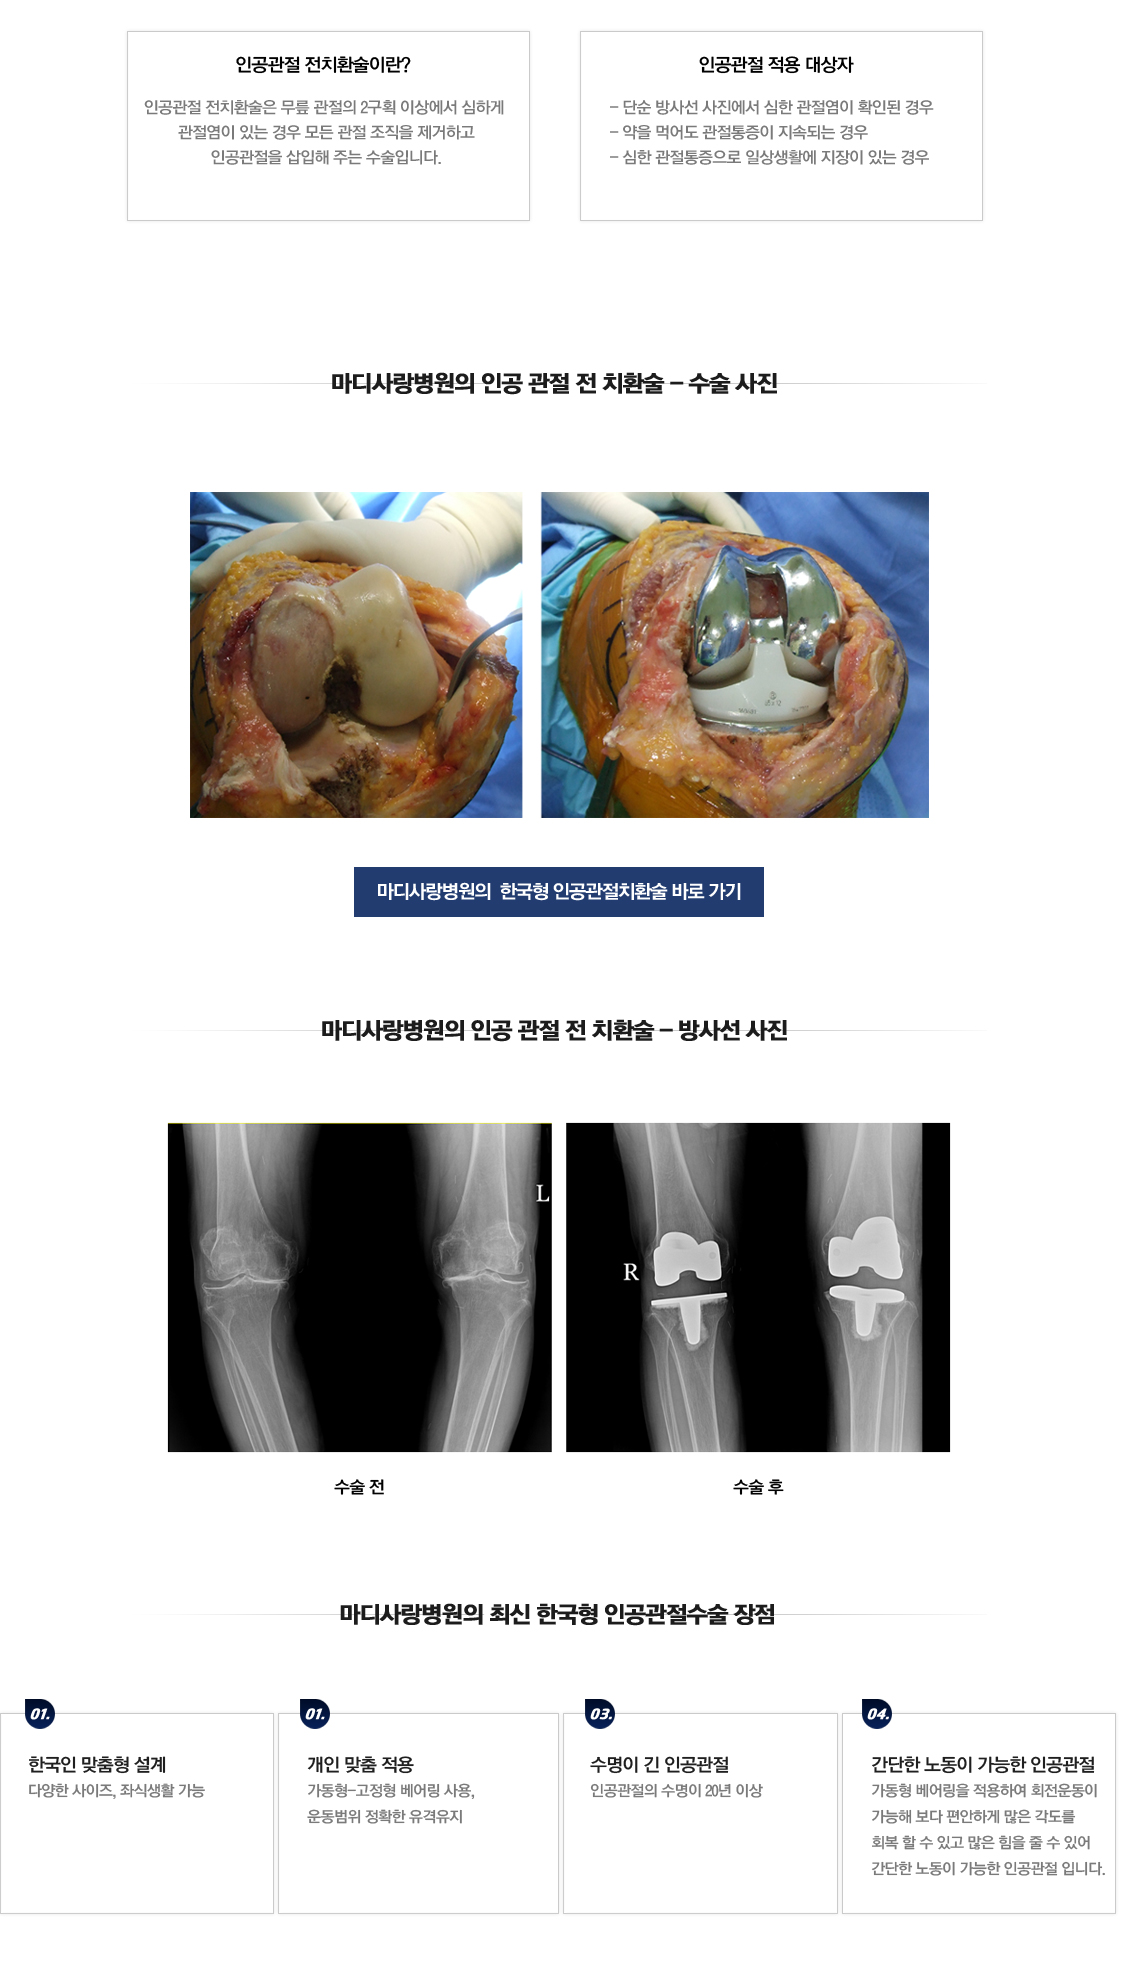

人工全膝关节置换术

人工关节全部置换术